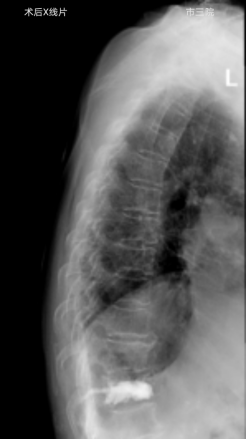

外二科收治了一位82岁的老年女性患者,患者摔倒后因腰部疼痛不能下床活动,在家长期卧床5个月,期间外用膏药,效果不佳,老人虽八十多岁,但受伤前身体硬朗,自己能够洗衣、做饭、赶集等,自从摔伤后不见好转卧病在床,子女们轮流照顾老人,打破了原本平静的生活,眼见老人下不了床子女们心急如焚,四处打听创伤小恢复快的治疗办法,经人介绍来到我院外二科就诊,磁共振检查显示患者胸12椎体压缩性骨折,椎体压缩性骨折已经5个月了仍未愈合,已经形成kummell 病,骨折基本不能愈合,此病首选经皮穿刺骨水泥注射椎体成形术治疗,创伤小、可迅速恢复自理生活,经与患者及家属沟通后同意手术治疗,就诊当天就办理了住院,住院后赵东主任医师对老人进行了全面查体,对老人家原本患有“冠心病、糖尿病”,积极联系内科会诊,完善术前检查做好充分术前准备。术中C型臂准确定位后,局麻下5mm皮肤切口,赵东主任医师顺利打入椎体骨水泥,韩克伟医生询问患者有无不适,患者诉腰部疼痛症状消失,术后第二天,患者佩戴胸腰护具下床独立行走,露出了久违的笑容。